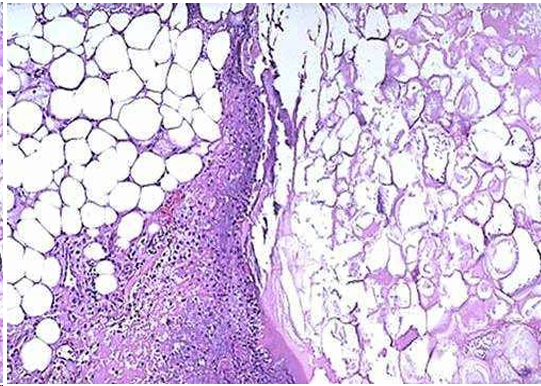

Mas información: Necrosis de la grasa, blanquecino, crepita, reflectante, seco y firme. Se diferencia mal de la grasa normal, puntitos mas claros. Suele ocurrir en pancreatitis, grasa abdominal, por traumatismos o dieta